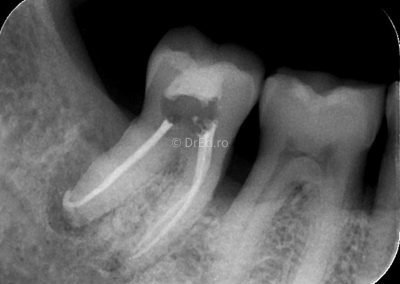

Galerie

Toate imaginile, fotografiile și radiografiile publicate pe acest site sunt protejate prin drepturi de autor și constituie proprietatea exclusivă a Dred.ro.

Aceste materiale sunt furnizate exclusiv în scop informativ și educațional și nu conțin date cu caracter personal sau informații care permit identificarea pacienților, în concordanță cu legislația privind protecția datelor cu caracter personal și GDPR.

Reproducerea, copierea, distribuirea, publicarea, transmiterea, modificarea sau orice altă utilizare, integrală ori parțială, a acestor materiale, în orice formă și prin orice mijloace, fără consimțământul prealabil scris al titularului drepturilor, este strict interzisă și poate atrage răspunderea civilă și/sau penală, în condițiile legii aplicabile privind drepturile de autor și protecția proprietății intelectuale.